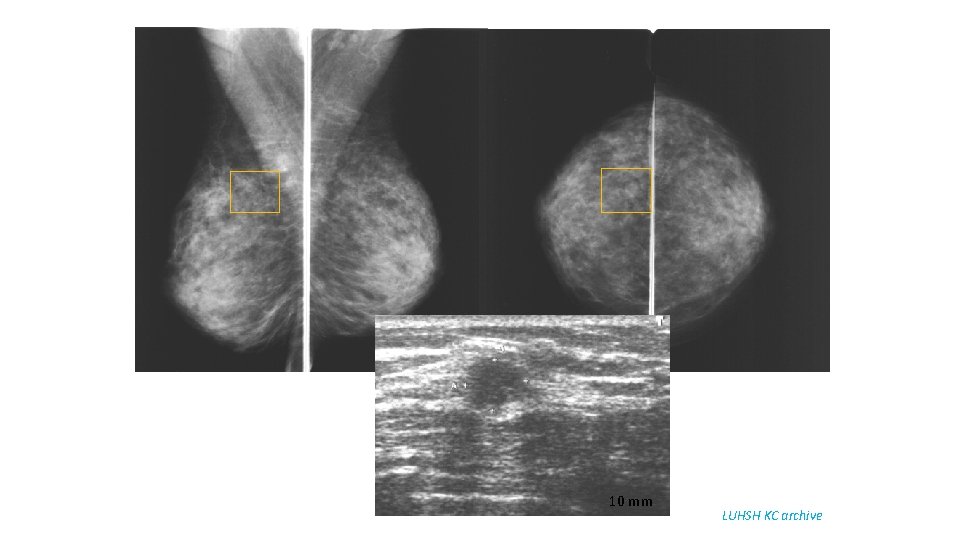

10 mm LUHSH KC archive

68 y old patient. Since 2003 yearly breast US – normal. 2009 - right nipple retraction. The first mammography examination: Ca lobulare infiltrativum LUHSH KC archive